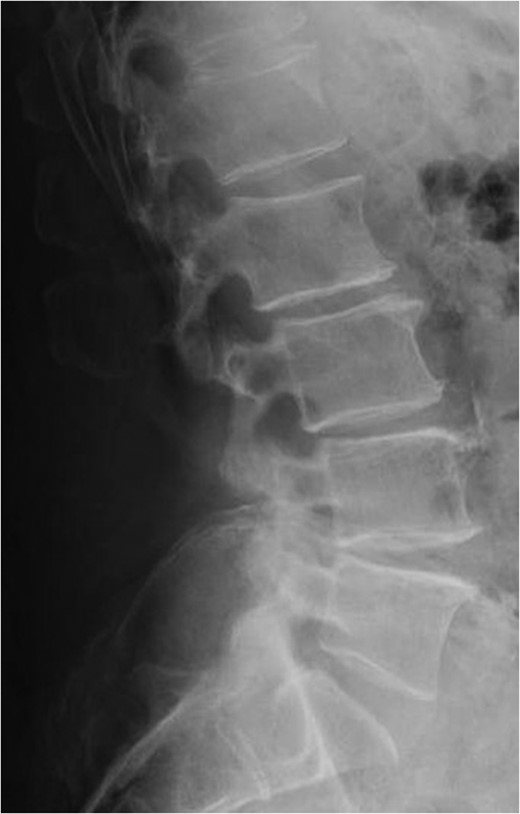

Standing neutral lateral lumbar radiograph obtained the day following the patient's L4–S1 revision decompression and posterior instrumented fusion with TLIF performed at each of these revised levels. A moderate correction of the prior L4-5 anterolisthesis was achieved and the patent's spine and construct appear stable.